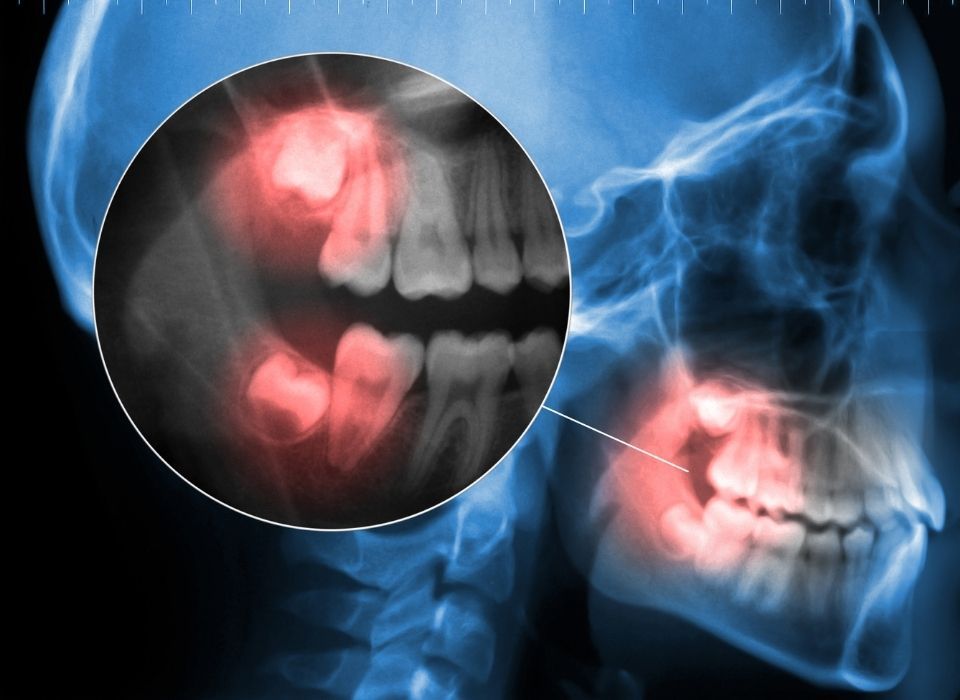

Oral surgery may be recommended when a tooth is too damaged to restore, when infection needs to be addressed, or when a surgical approach is the best way to protect surrounding teeth and gums. Some procedures are planned in advance, while others are needed urgently due to pain or swelling. Our team takes time to explain why surgery may be recommended, what you can expect, and how we will support your comfort throughout the process.

During your consultation, we evaluate your oral health, review any imaging needed, and create a treatment plan based on your needs. We also provide clear aftercare instructions and follow up support so you feel confident during healing. Oral surgery can help with removing damaged or infected teeth, treating impacted wisdom teeth, supporting implant placement with bone or gum procedures, improving comfort when tooth structure is limited, and restoring oral health when multiple concerns are present.